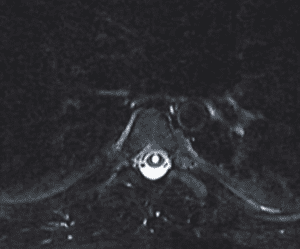

As in her case, MRI imaging, with heavily weighted T2 Fat-Saturated Sequences (3D-T2WI-FS) provide a very high accuracy for the CSF leak presence into the epidural space. Multiple imaging sites are usually identified, although at surgery or with dynamic CT myelography, only one site is found.

Fig 1. MRI myelogram with fat saturation showing multiple fluid areas along nerve root areas in the high and low lumbar region, consistent with CSF leaks.

The thin Dura in patients with EDS can dehisce at any point. Other causes include on osteodiscophyte penetrating the Dura, or rupture of a spinal nerve root diverticulum. Recent appreciation of other mechanism of Spontaneous Intracranial Hypertension (SID) includes CSF-Venous Fistula.